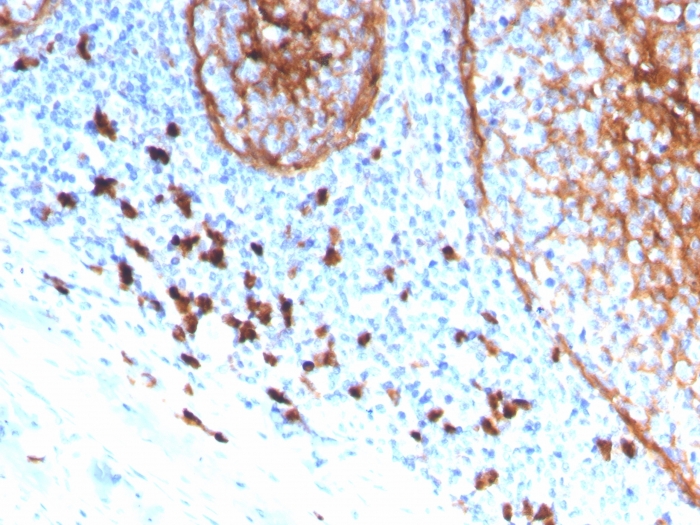

Formalin-fixed, paraffin-embedded human tonsil stained with CD11b Monospecific Mouse Monoclonal Antibody (ITGAM/3339).

CD11b is a cell adhesion molecule that acts as a receptor for cell surface ligands such as intracellular adhesion molecules (ICAMs) or soluble ligands. Integrins are heterodimeric proteins that contain an a chain and b chain. Integrin M2 is important in the adherence of neutrophils and monocytes to stimulated endothelium, and also in the phagocytosis of complement coated particles. The protein CD11b has been implicated in the various adhesion-related interactions of cells such as monocytes, macrophages, natural killer (NK) cells, and granulocytes. It is part of a heterodimer that consists of CD11b and CD18. It also modulates the uptake of complement-coated particles within the cell. It is commonly used as a microglial marker in tissues derived from the nervous system.